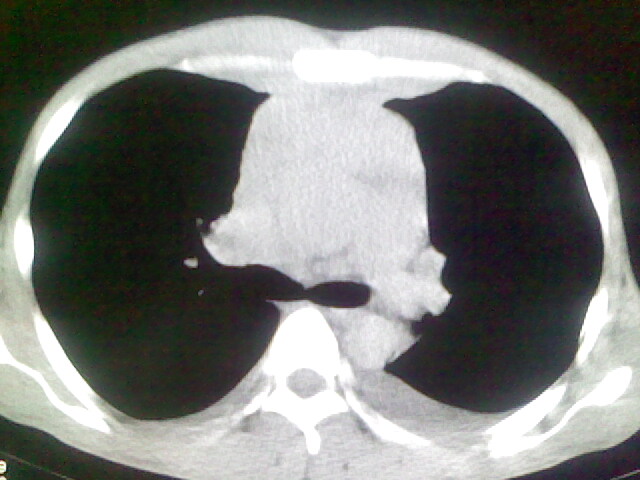

以下是引用杀毒软件在2008-9-3 6:11:00的发言:[br]侵袭性胸腺瘤------一般不侵到气管旁[br][br]考虑----纵隔淋巴瘤,心包及胸膜受累

以下是引用wzr在2008-9-3 5:30:00的发言:[br]侵袭性胸腺瘤

以下是引用随光逐影在2008-9-3 7:07:00的发言:[br]1)考虑淋巴瘤可能。2)双侧胸腔积液(以左侧为甚)。3)心包积液。